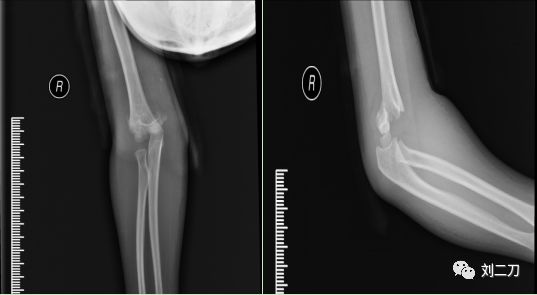

肱骨髁上骨折中医治疗及其康复训练 刘二刀 微信公众号文章阅读 Wemp

新华康复科普第174篇 非同小可的儿童肱骨髁上骨折 上海新华医院康复医学科 微信公众号文章阅读 Wemp

肱骨髁上骨折小儿肱骨髁上骨折的症状是什么 妈妈网

揭秘 肱骨髁上骨折 零切开 每日头条